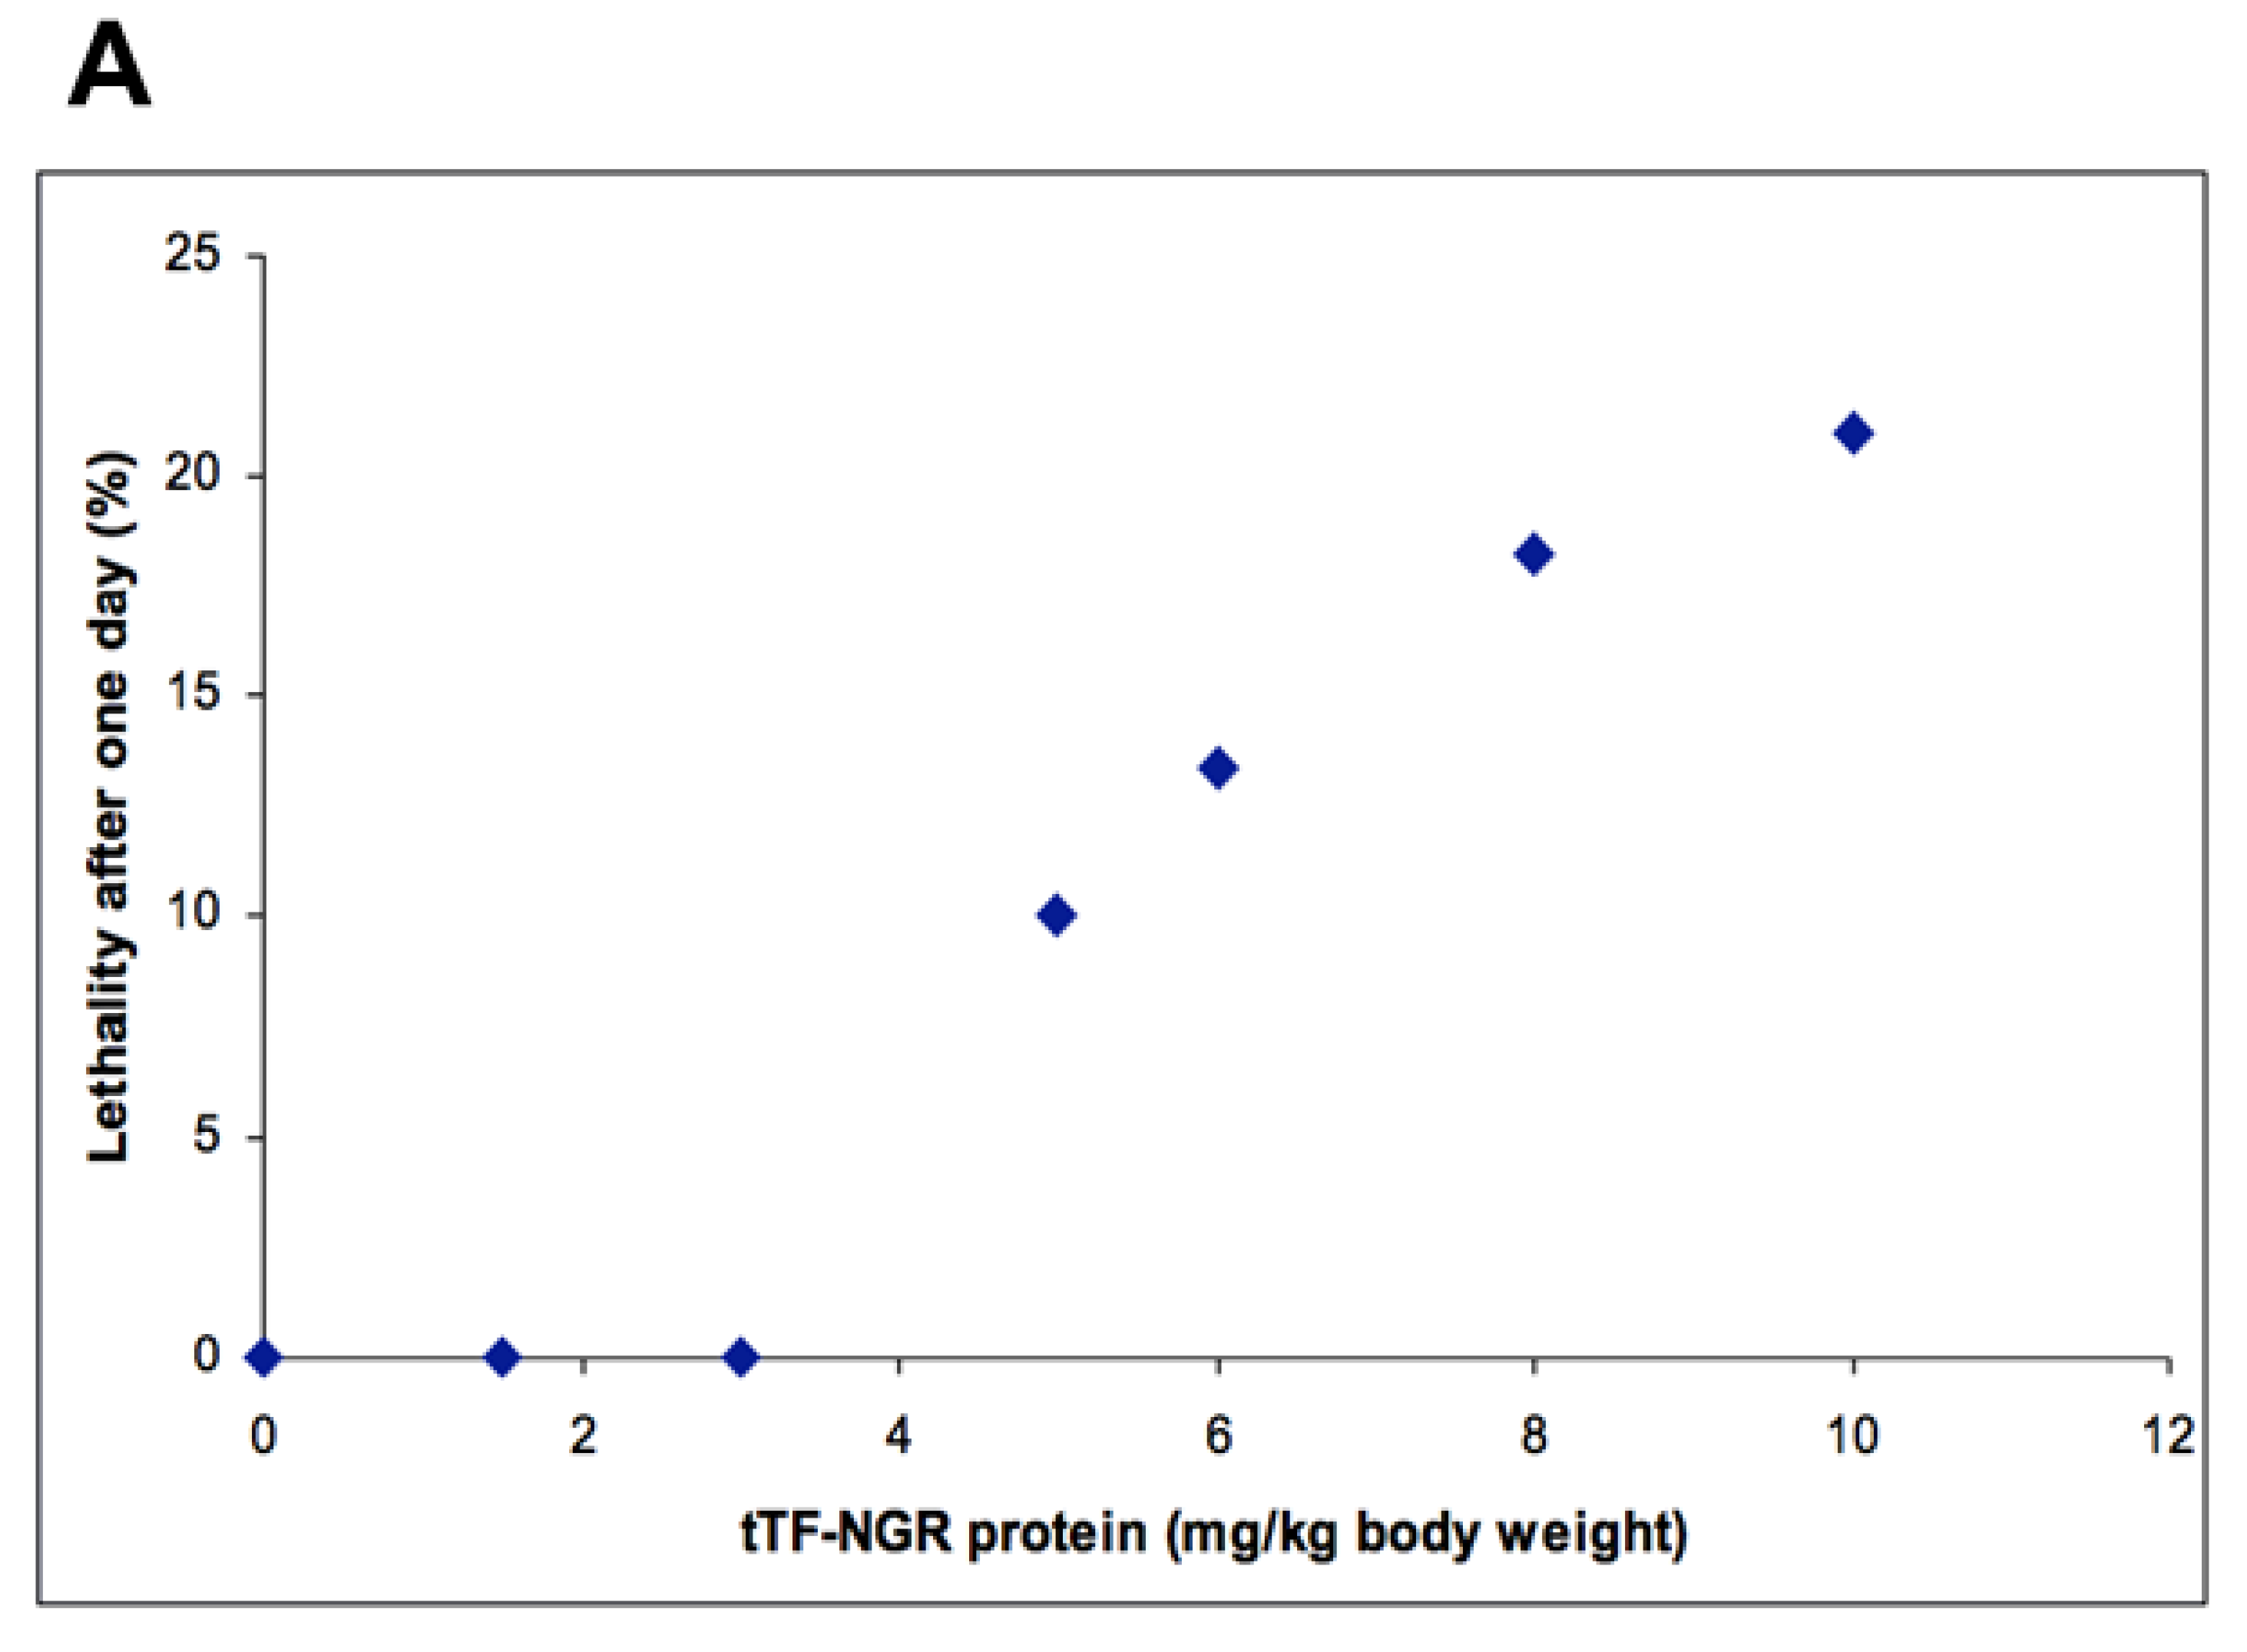

3.1. Academic Toxicology Studies for Intravenous Application of tTF-NGR in Mice

3.2.1. Mouse Studies

4.3.1. Mouse Data